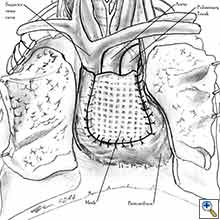

Medium and large-sized (Figures 1a, 1b) defects generally result after pneumonectomy for advanced central lung tumours which invade the pericardium (T3 invading pericardium), thus requiring reconstruction (Figure 1c). To achieve a curative resection, negative pericardial resection margins must be obtained and checked microscopically. More invasive tumours (T4 invading cardiac structures) require partial atrial resection and pericardiectomy associated with pneumonectomy.

| Figure 1c: Intraoperative aspect of pericardioplasty with Marlex mesh after right completion pneumonectomy with partial pericardiectomy. |

Video 1 depicts a pericardial reconstruction with Marlex after a right completion pneumonectomy with pericardiectomy for lung adenocarcinoma (see also Figure 1). The technique of pericardial reconstruction after the resection of invasive mediastinal tumours is illustrated in Figures 8a-c). Video 2 depicts a pericardial reconstruction with Mersilene mesh after the resection of a malignant thymoma invading the anterior pericardium (see also Figure 4b). The technique of right pericardial reconstruction after extrapleural pneumonectomy is illustrated in Figures 9a and 9b). Video 3 depicts a pericardial reconstruction using Gore-Tex Dual Mesh after a left extrapleural pneumonectomy (see also Figure 3). Care must be taken to prevent constriction (Figure 10).